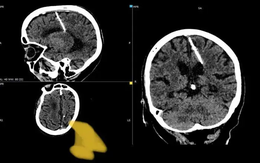

Bà cụ sống khỏe với cây kim trong não suốt 80 năm

Khi chụp CT, các bác sĩ ở vùng Viễn Đông Nga rất bất ngờ khi phát hiện cây kim dài gần 3cm trong não bà cụ 80 tuổi.